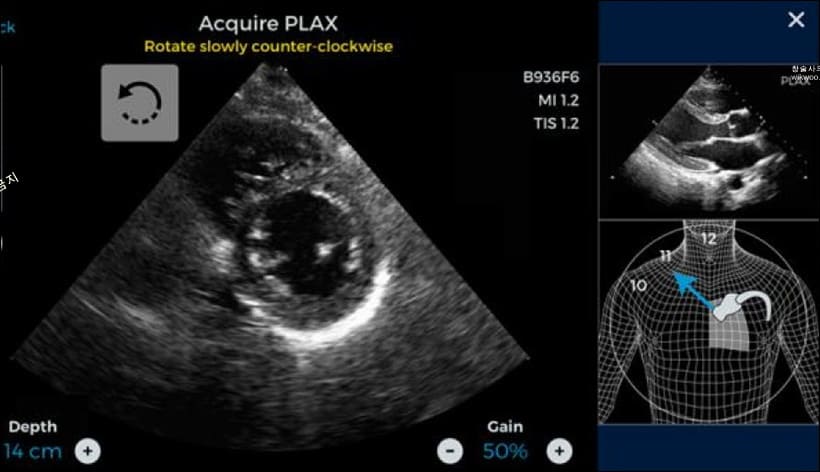

심장초음파 검사는 인체에 해롭지 않은 초음파를 심장에 보내어 반사돼서 돌아오는 초음파를 이용하여 영상을 만들어 심장의 구조와 기능을 분석하는 검사 기법입니다.

몸속으로 의료 기구를 삽입하지 않고 심장의 내부 구조와 기능, 움직임 등을 눈으로 직접 볼 수 있으며, 임산부나 유아도 안심하고 검사할 정도로 부작용이 없이 안정적인 검사 방식입니다.